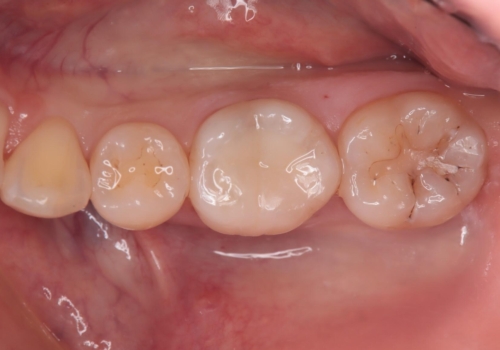

詰め物の下が黒いのが気になる セラミックインレー修復

- 定期健診の際に、他院の詰め物の下が黒くなっているのが気になるとのことで、セラミックインレーで治療し直したケースです。色調も調和しており、術後の経過も良好です。